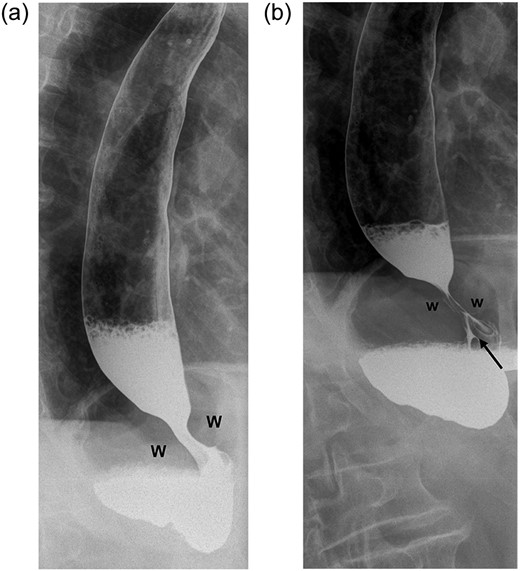

A 65-year-old female patient had undergone repair of a large hiatus hernia by laparoscopy with posterior cardiopexy and 360° fundoplication. Routine contrast swallow on Day 1 showed good passage of contrast through the fundoplication (Fig. 1a). On Day 2 post-operatively, saliva regurgitation occurred and repeat contrast study revealed a hold up at the level of the wrap (Fig. 1b). Intravenous dexamethasone (Merck Sharp & Dohme Laboratories-Chibret, France) administration at a dose of 8 mg daily was instituted for 72 h. Forty-eight hours later, oral fluid was tolerated allowing discharge and diet was upgraded to full fluids a week later. Recovery was progressive and uneventful with return to normal diet.

(a) Contrast swallow on Day 1 following posterior cardiopexy and 360° fundoplication demonstrating adequate passage of contrast through the wrap (W=right and left folds of the wrap). (b) A repeat contrast swallow in the same patient 24 h later revealing a hold up at the level of the wrap caused by oedema. The oesophagus above the wrap is dilated. A thin trickle of contrast (black arrow) is seen to come through the fundoplication.